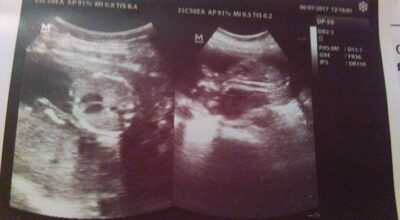

Mi precioso Heitan Miguel